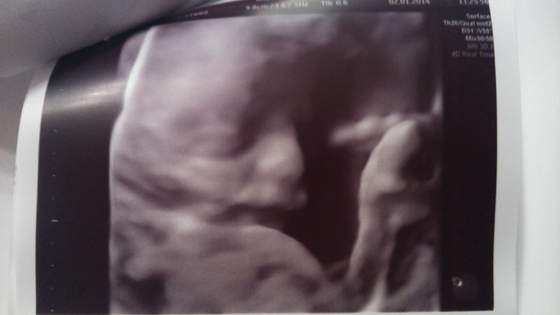

udanej wizyty :-)Piekna fotkaNo I udalo sie tez fotke wkleic po kilku probach!!! Ufff

a to nasza maleńka

Fajne zdjecia a zwlaszcza to w w 4d takie wyrazne do kogo podobna?